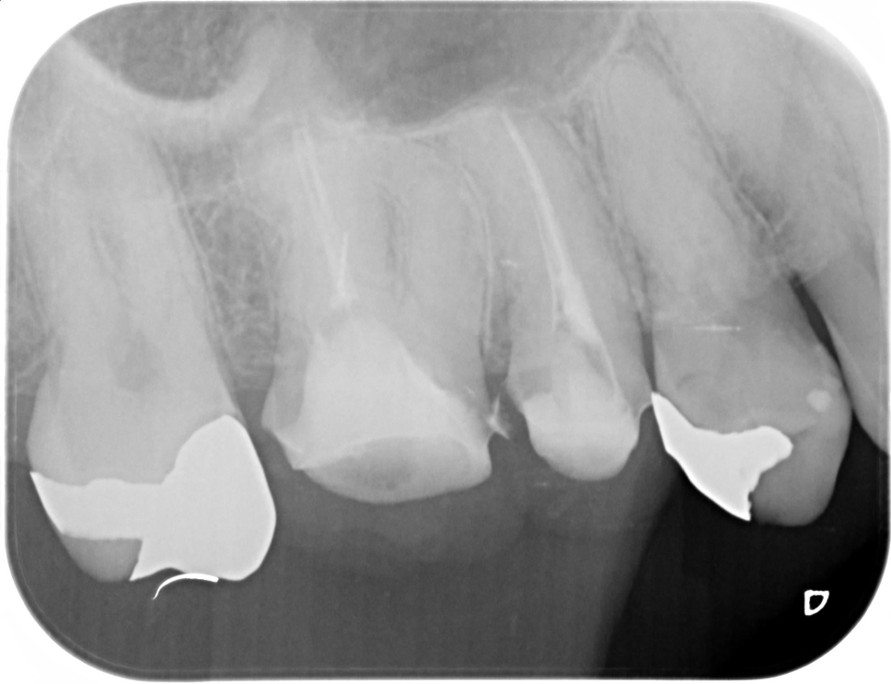

症例1:パーフォレーションリペア症例

(歯の中に大きな穴が空いてしまっているのを埋めて再生を促す治療)

歯に穴が空いていて骨に炎症がある状態 |

CTでも歯の周囲に骨がないのが分かる。 |

BEFORE |

AFTER |

人為的根穿孔を起こした部分に感染を起こしており、歯周ポケットが9㎜ありました。 ラバーダム防湿とマイクロスコープを使用して丁寧に治療を行いました。 殺菌性があり歯を補強することのできるMTAという根管充填材料を使用して、歯周ポケットは2㎜に改善しました。 |